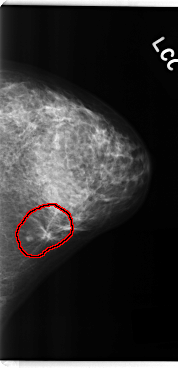

C_0222_1.LEFT_CC

LEFT_CC LINES 4776 PIXELS_PER_LINE 2304 BITS_PER_PIXEL 12 RESOLUTION 50 OVERLAY

FILE: C_0222_1.LEFT_CC.OVERLAY

TOTAL_ABNORMALITIES 1

ABNORMALITY 1

LESION_TYPE MASS SHAPE IRREGULAR MARGINS SPICULATED

ASSESSMENT 5

SUBTLETY 5

PATHOLOGY MALIGNANT

TOTAL_OUTLINES 1

BOUNDARY